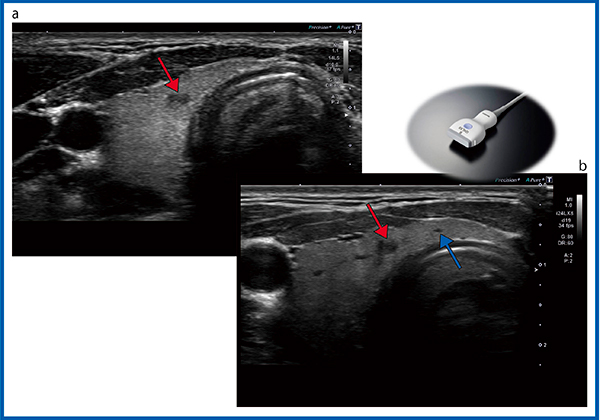

24MHz超高周波リニアプローブ

Aplio i800の新しいリニアプローブ「PLI-2004BX」は,8〜24MHzに対応した超高周波プローブである。24MHzの高周波によって,体表に近い部分から深部まで高分解能の画像が得られる(図11 b)。通常の周波数で見た甲状腺では,囊胞(↓)が確認できるが,胸壁に近い部分にはなにも見つからない(図11 a)。しかし,24MHzの超高周波で観察すると,胸壁に近い部分に小さな囊胞(↑)が確認できる。超高周波プローブを使うことで,胸部の浅い領域の腫瘍やリンパ節など,より表在に近い領域の観察が可能になると考えられる。

図11 24MHz超高周波プローブ「PLI-2004BX」

a:10MHz(PLT-1005BT) b:24MHz

超音波ガイド下穿刺について

超音波検査で結節性病変が発見された場合の精査の手順としては,充実性か濾胞性かに分けて判断されるが,充実性結節の超音波診断フローチャートでは最大径が>5mmかつ≦10mmで悪性が強く疑われる場合,>10mmかつ≦20mmでは悪性疑いの場合,>20mmの場合は原則として穿刺吸引細胞診(FNAC)を行う1)。超音波ガイド下で行われる穿刺方法には平行法と交差法がある。平行法ではガイドラインが表示されるため経験が少なくても穿刺が可能だが,交差法ではガイドラインがなく熟練が必要とされる。そこで,当院では平行法を中心に施行しているが,表在に近いリンパ節では距離と角度がないことから,画像の端に腫瘍が来ることになり,針先の確認が難しかった。これに対して,Aplio i800では,交差法で穿刺が可能なアタッチメント(アダプタ)と針先のガイド機能が搭載された。表在から0.5mm,1.5mmといった浅い領域でも針先の位置をガイドした正確な穿刺ができ,交差法での穿刺についてもサポートが可能になった。